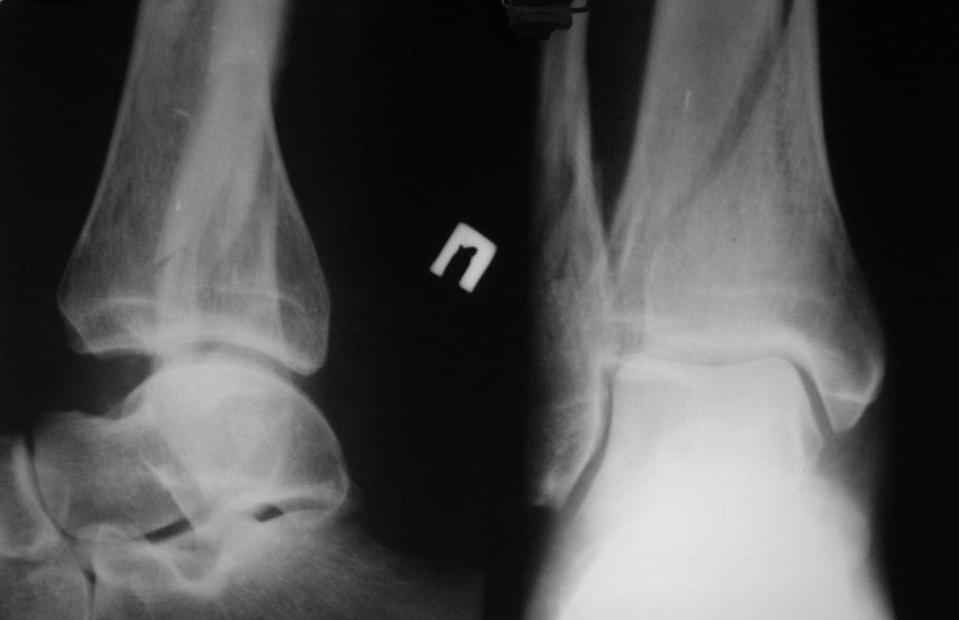

[Ortho] перелом пилона. тактика лечения

прошу прощения за то, что забыл приложить снимки

Имя     : IMG_3044_12.jpg